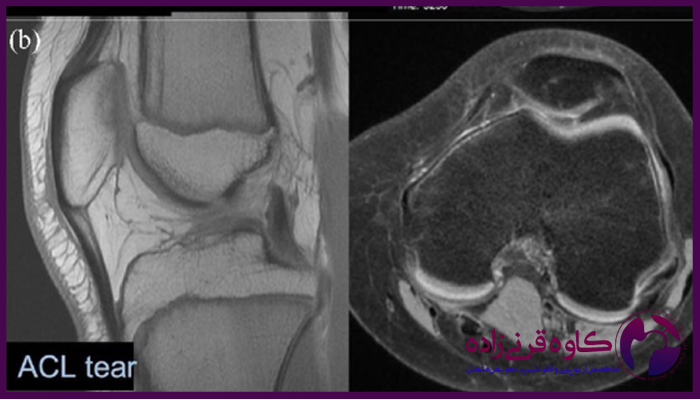

برای تایید تشخیص و بررسی شدت آسیب، معمولا از تصویربرداری به ویژه ام آر آی استفاده میشود که پارگی رباط ها و سایر آسیب ها را به طور دقیق نشان میدهد. در برخی موارد، آرتروسکوپی زانو نیز برای بررسی وضعیت داخلی زانو و تعیین روش درمانی مناسب مورد نیاز است.

عکس ام ار ای پارگی رباط زانو